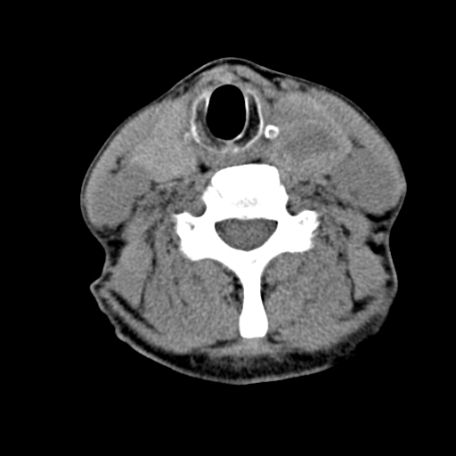

标题: CT24010:患者女56岁双侧甲状腺摘除术后一月复查,患者现感 [打印本页]

标题: CT24010:患者女56岁双侧甲状腺摘除术后一月复查,患者现感

甲状腺术后复发,现在甲状腺区域仍有密度不均匀之软组织密度影。

甲状腺区域密度不均匀密度影,应该是术后改变,要鉴别是否复发,建议增强检查。

“甲状腺摘除术后一月复查”,有病理吗?考虑术后复发,可能是恶性,颌下及左侧颈部淋巴结有肿大。

考虑术后复发,并颈部淋巴结肿大。请结合临床。

双侧甲状腺肿大,周围结构不清,术后复发时间有点短,考虑出血并感染。